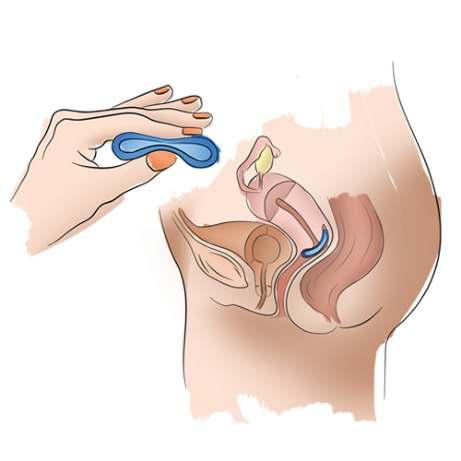

7.1.1.Métodos de barrera

Diagragma

El diafragma y los capuchos son métodos que tienen la ventaja a diferencia de los preservativos de poder ser usados en vario coitos sin necesidad de movérselo o cambiárselo, una vez retirado de la vagina se lava y se guarda pudiéndolo utilizarle más o menos

ANILLO VAGINAL

Único de administración vaginal mensual, es un anillo transparente, suave y flexible el cual se lo coloca por la misma usuaria por vía vaginal, liberando diariamente dosis bajas de hormonas.